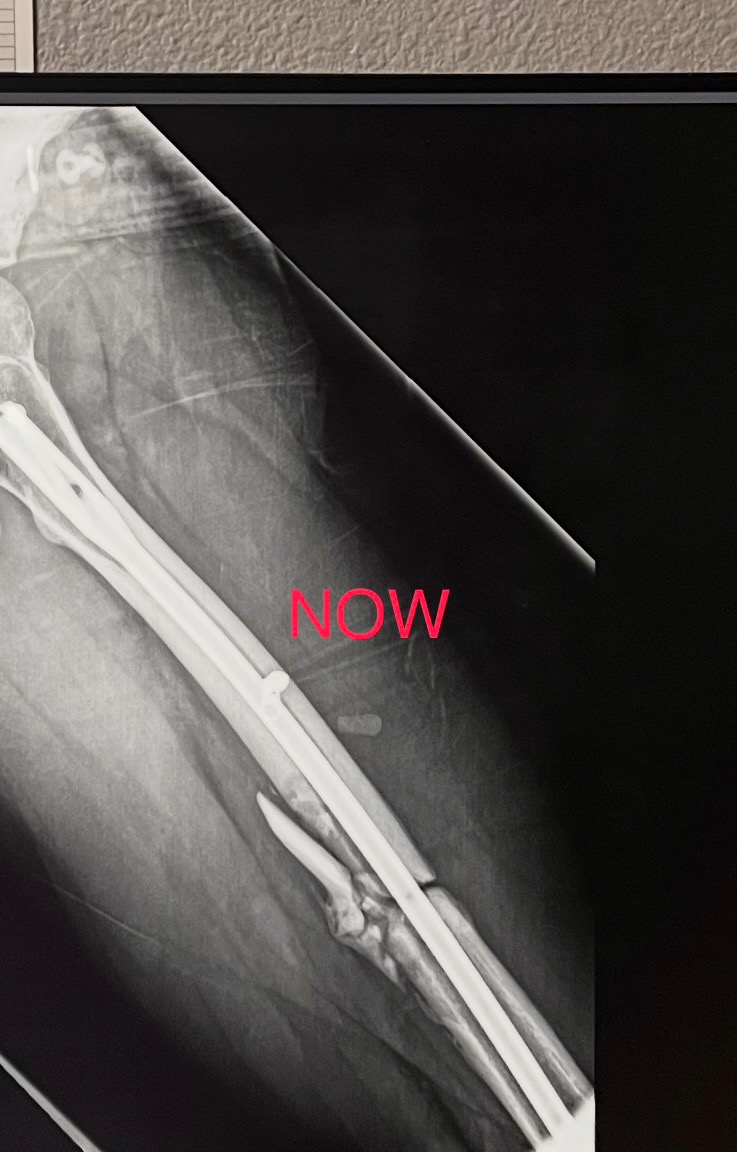

Leo’s injuries are severe—he shattered his left leg and required emergency surgery to insert a rod with three screws. The doctors have told us that two pieces of his bone may never fully heal or connect to the rod, making his recovery uncertain and challenging. Leo now faces a long road of physical therapy, ongoing doctor visits, and significant medical expenses. He will need help with living costs while he focuses on healing and regaining his strength.